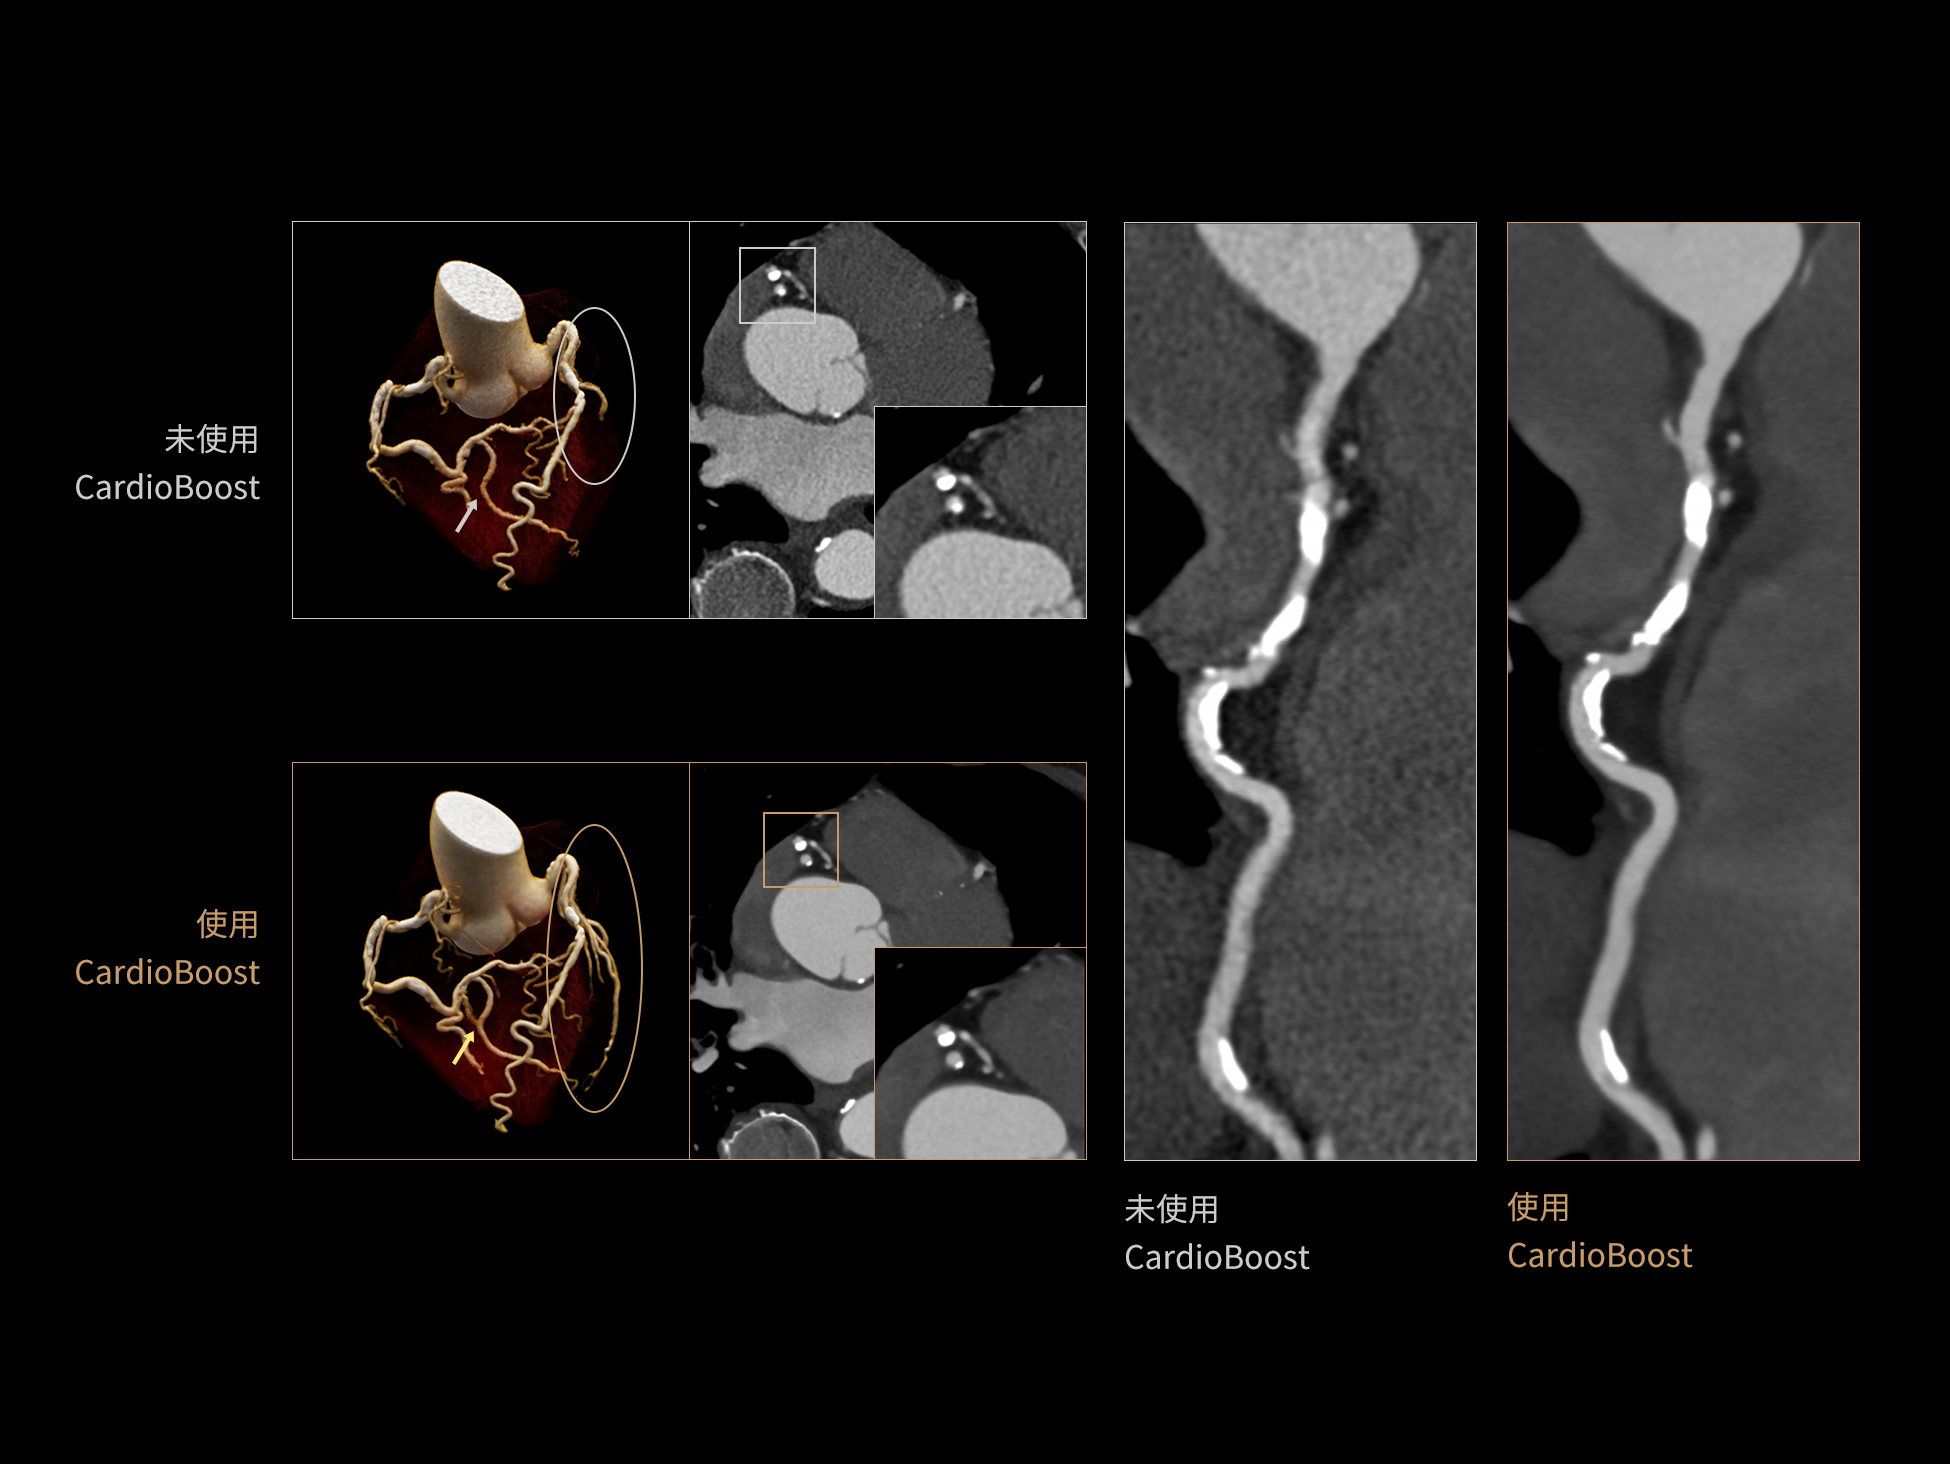

CardioBoost:专属网络设计,重塑心脏影像表现

uCT 868 搭载联影最新一代 uSense 人工智能平台,将智能化深度融入 CT 扫描全流程,从感知细微生理运动到精细结构探测,再到多场景诊疗优化。以 AI 为核心驱动力,uSense 重塑成像各环节,打造高效、高清的智慧扫查体验。在心脏成像领域,uSense 结合宽体探测器、心脏专研AI重建算法与AI冠脉运动追焦技术,在保持低剂量的同时,有效抑制运动伪影,精准呈现软斑块、混合型斑块及支架细节,助力冠脉成像惠及更多患者。针对多科室疾病临床应用场景,uSense 平台提供全方位的智能解决方案:包括头部运动伪影智能校正、金属植入物伪影抑制、扫描视野扩展等先进算法。这些创新技术使 uCT 868 能够构建覆盖全场景的智能诊疗体系,持续拓展 AI 赋能医学影像的边界。